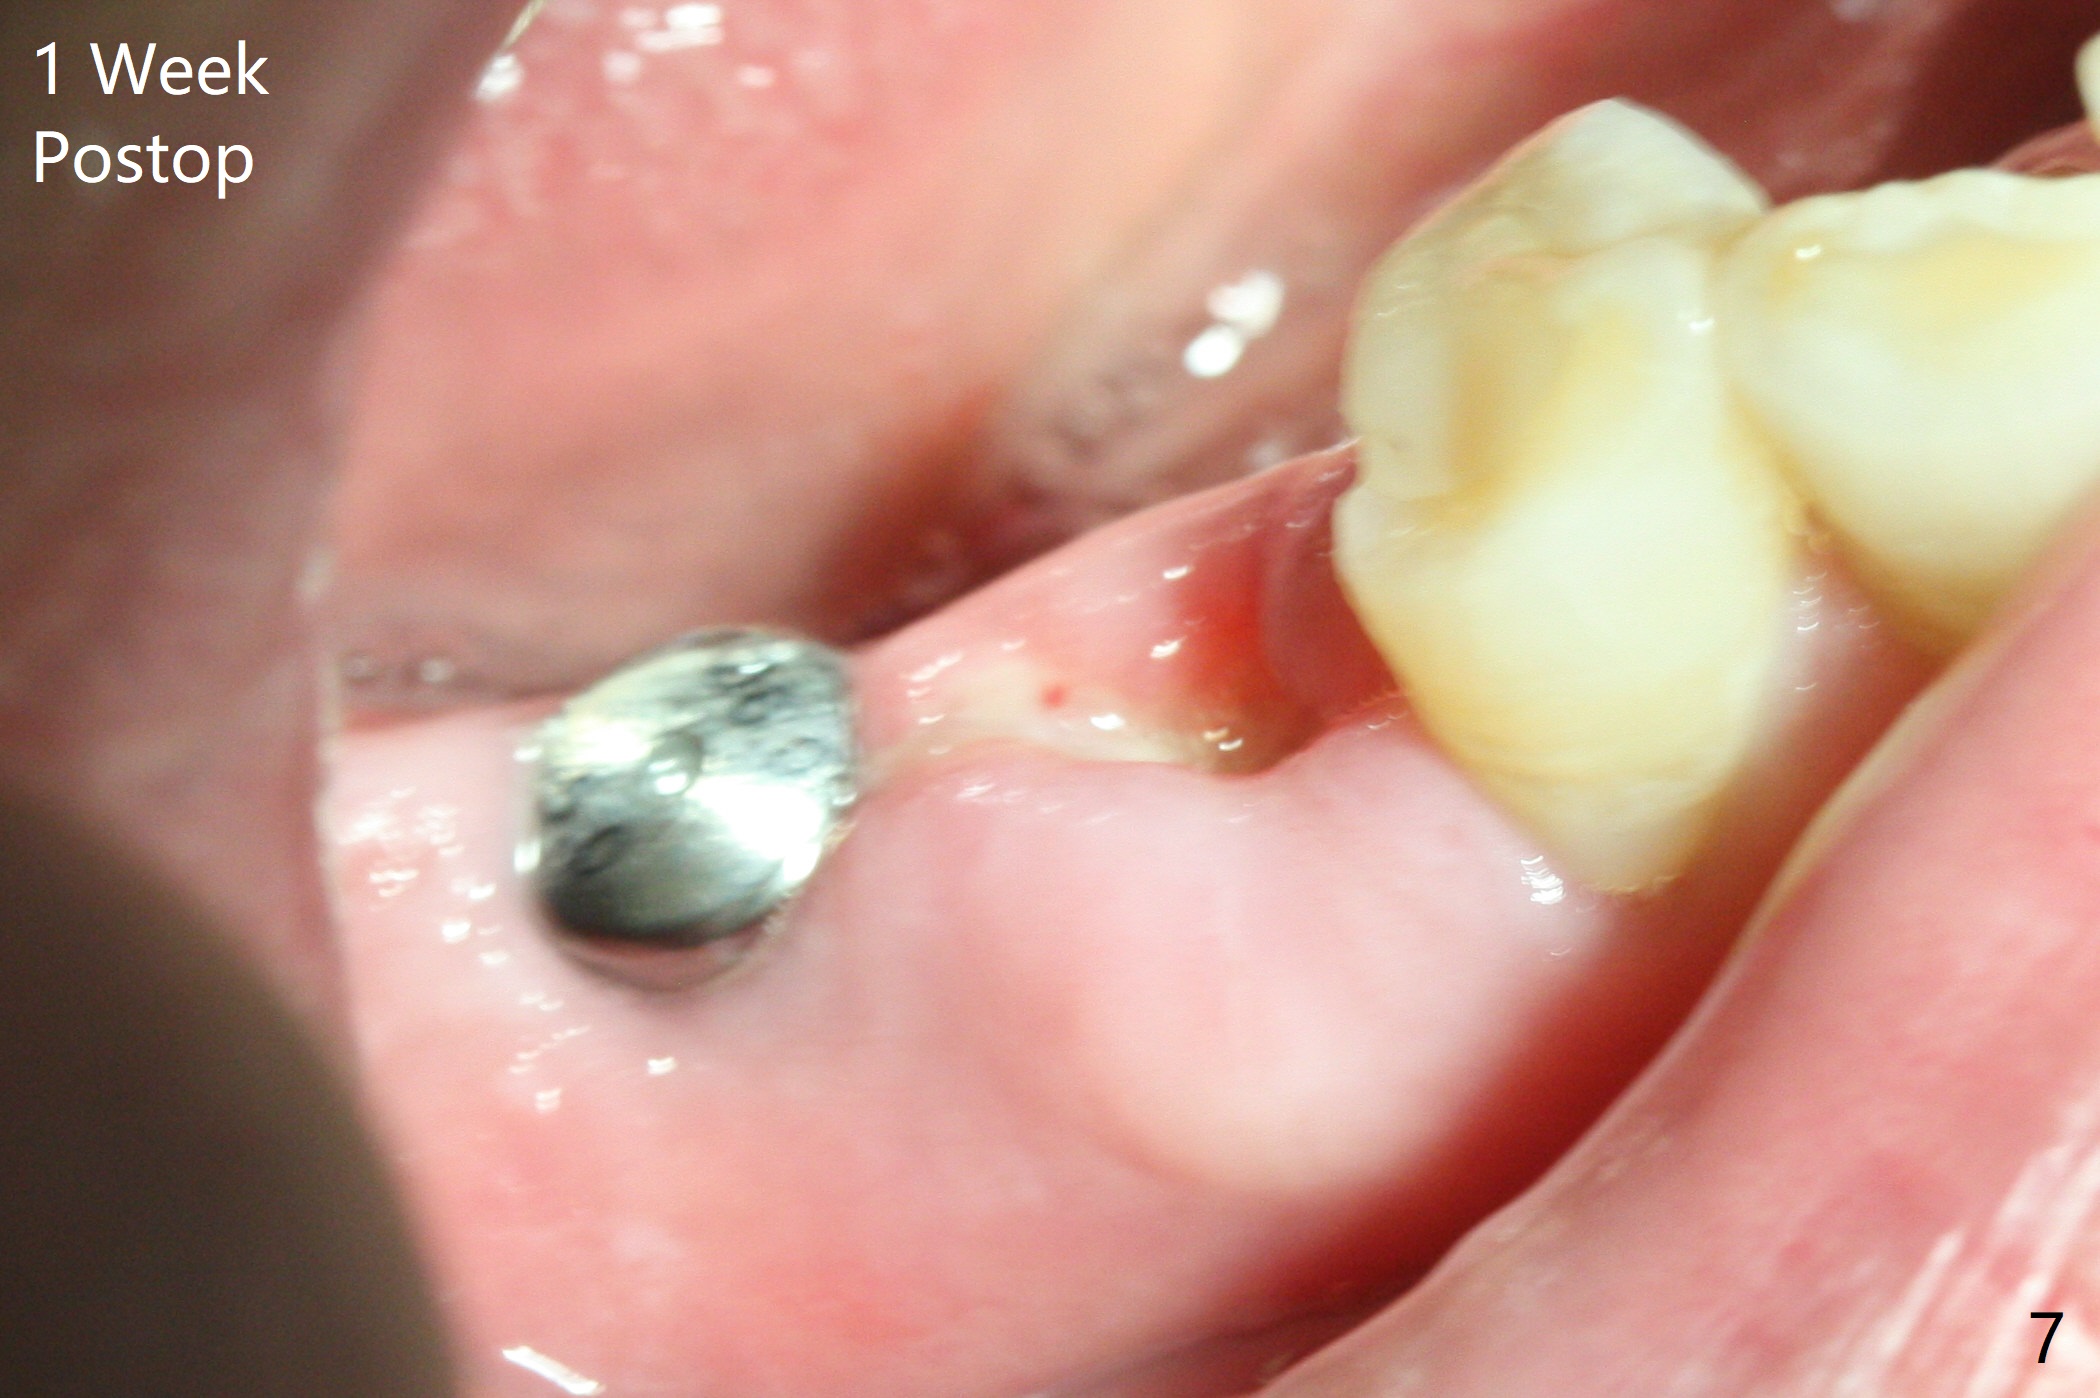

An endodontist refuses RCT retreatment at #29 because of short root. The patient is hesitant about apicoectomy. After discussion of advantages and disadvantages of the latter vs. extraction and implant, the patient chooses the extraction. The latter turns out to be smooth with socket preservation (Fig.4, 5 *). Immediately postop PA shows bone loss at #30 and minor degree around the apex of #31 implant (Fig.4 <), which is probably related with hard bone and bone necrosis due to heat. The headache disappears 1 week postop (Fig.6). The patient does not take pain medication. There is no percussion at #30 (Fig.7). The healing abutments are stable. The patient will return for #30 and 31 restoration nearly 4 months postop and 2 months post #29 extraction. Splinted provisional will be placed if the implants heal. Impression will be taken for #29 guide 4 months post socket preservation. After re-analysis of CT, it appears that a long implant (4x15 mm to gain 3.9 mm fixation in the native bone) will be placed free hand at #29 four months post socket preservation (Fig.8). The bone loss around the implants at #30 and 31 persists 3.5 month postop, while the socket heals at #29 2 months post socket preservation (Fig.9). When the healing abutments with plaque are removed, there is granulation tissue around the gingival cuffs with tenderness. The abutments with heavy plaque (similar to that in Fig.7) are reloaded after cleaning with OHI. The patient returns for CT and impression for #29 guide 3.5 months post socket preservation and 5 months post implant placement. While bone necrosis remains severe at #30, the socket at #29 seems to have healed (Fig.10). Oral hygiene improves with healthy gingiva, but there is tenderness when a cementation abutment is placed. Implant design before and after extraction at #29 (Fig.11,12). Gingiva becomes inflamed at #31 when a splinted provisional is being worn to intrude the opposing supraerupted teeth; bone resorption remains severe in the previous distal socket and the mesial necrotic area (Fig.13 S, N). Pain persists after placement of a healing screw. In spite of severe bone loss, especially distal, the buccal plate is present. When the implant at #31 is removed, there is a large defect with granulation tissue apicobuccal to the buccal plate, corresponding to the presumptive mesial necrotic area (Fig.13,14 N). Vanilla graft mixed with PRF ("sticky bone" too rigid) is placed in the defect, followed by a piece of PRF membrane and 6-month one. The pain appears not to reduce and nearly 1 month later transfers to the buccal of #30.